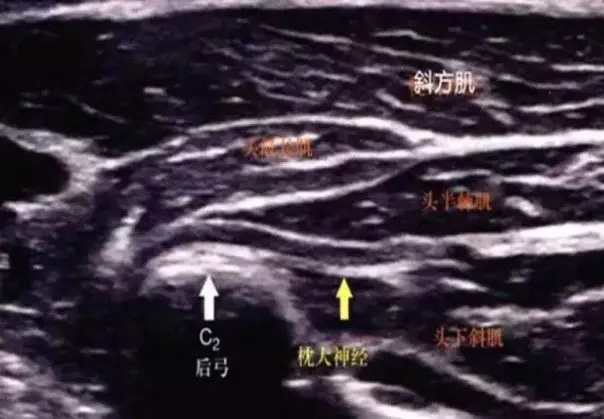

1、枕大神经出口处:枕大神经是第二颈神经后支的感觉分支,与枕小神经共同支配枕部皮肤直至头顶感觉,由C2神经发出后在寰枢关节后内侧的寰枢间骨筋膜裂孔出椎管。枕大神经穿斜方肌腱至皮下,分布于枕部的皮肤,为混合性神经。如此神经受损则其支配区域的运动和感觉可发生障碍。

该处为头半棘肌、枕大神经的出口处,枕骨粗隆下,颈项酸痛者这两处—般均有显性应激点,按压时酸痛胀麻可向上波及整个后脑部。神经及节段:枕大神经、C2后支。